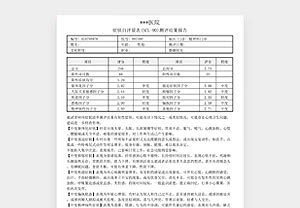

恶搞精神病诊断证明

中度抑郁症测评报告单

不孕不育DNA分析报告

¥60.00 -

告别千篇一律的整蛊套路,这里藏着数不清的脑洞玩法。我们精选医用级打印纸,从外观到触感都复刻真实质感,拿在手里的瞬间,逼真度直接拉满。超全素材库随心挑,覆盖多类型恶搞模板,不管是想上演 “惊喜官宣” 戏码,还是打造让人信以为真的趣味乌龙,从单人创意到多人脑洞组合,通通能满足。

关键在于无懈可击的逼真呈现。我们的打印件采用正宗医用光面纸,搭配数十款 4 周至足月的超写实设计(含双胎、三胎模板),为整蛊的可信度筑牢根基。

医用级光面工艺打印!6×8 厘米高端光面照片纸制作,还原照片级清晰画质。专为影视道具、节日恶搞、创意纪念等场景设计!